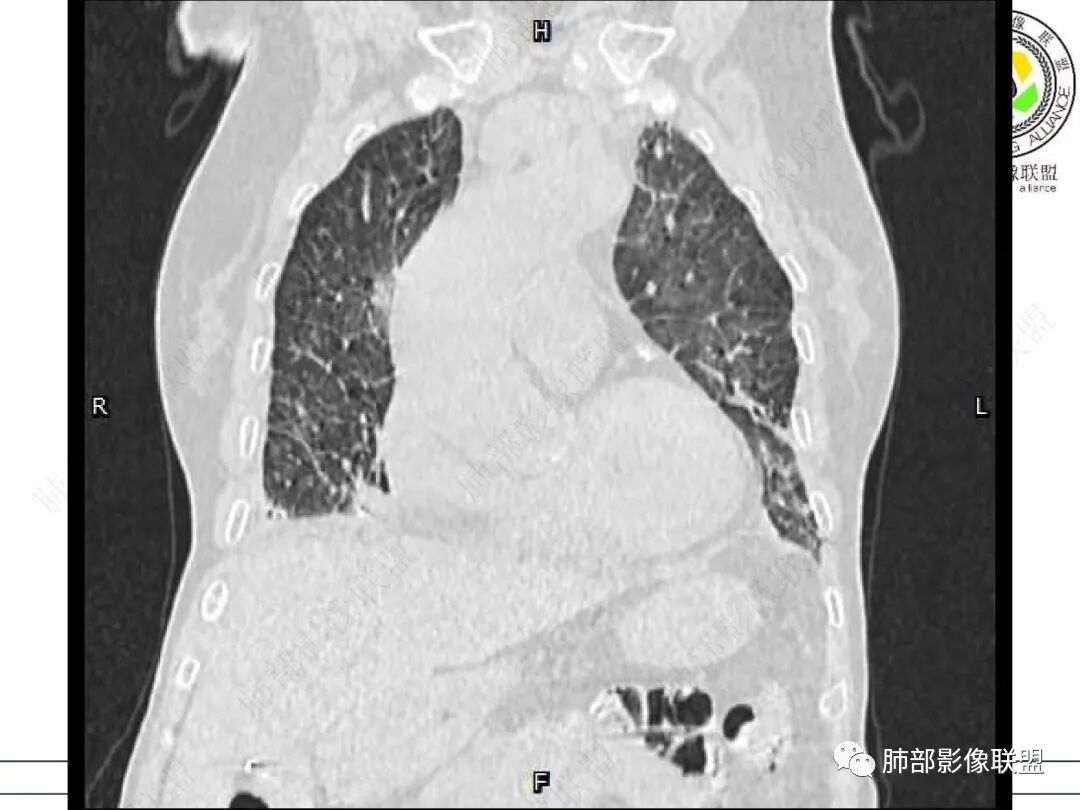

两肺叶后肋膈角区见多发蜂窝状结构破坏表现,双肺叶小叶间隔增厚,左肺上叶后段及舌段和右肺中叶胸膜炎性肉芽肿特点,双侧胸腔少量积液,有类风湿性关节炎治疗史,结缔组织相关性间质性肺病。

老年女性,类风湿关节炎病史多年。发热。以两肺下叶为主弥漫磨玻璃及网格状透亮影,透亮度减低,局部小蜂窝状改变;两肺胸膜下散在几枚实性病灶;双侧胸腔积液。考虑RA-ILDNSIP

两下肺多发蜂窝状表现,双肺小叶间隔增厚,双肺磨玻璃影及部分炎性肉芽肿表现,双侧胸腔积液,有类风湿性关节炎治疗史,结缔组织相关性间质性肺病。患者C反应蛋白和降钙素原都高,是否合并细菌感染

双肺下叶多发蜂窝影,双肺小叶间隔增厚,双肺磨玻璃影,双侧胸腔积液,有类风湿性关节炎,考虑结缔组织相关性间质性肺病,合并感染

①影像表现复杂:较弥漫间质性改变,对称磨玻璃密度为主,小叶间隔增厚,有一定重力分布趋势,未见明显纤维化,气囊及蜂窝位于肺边缘,未见典型“月弓征”。心脏影增大,双侧胸腔积液。

上肺斑片影、结节影,夹杂纤维条索影,边界清楚,新旧不等,胸膜牵拉明显等等,符合较典型继发性肺结核表现,但它却未必是此次就医主要责任病原体!